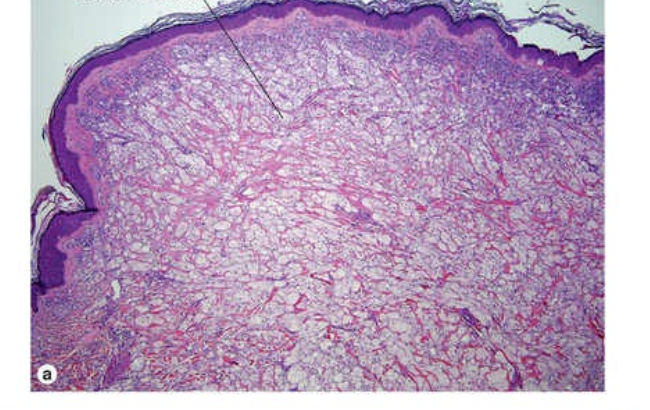

Epidermis = unremarkable Elongated, wavy spindled cells in the dermis, arranged parellel to the epdiermise Heavily pigmented Increased collagen Dx: Blue Cell Naevus - classic